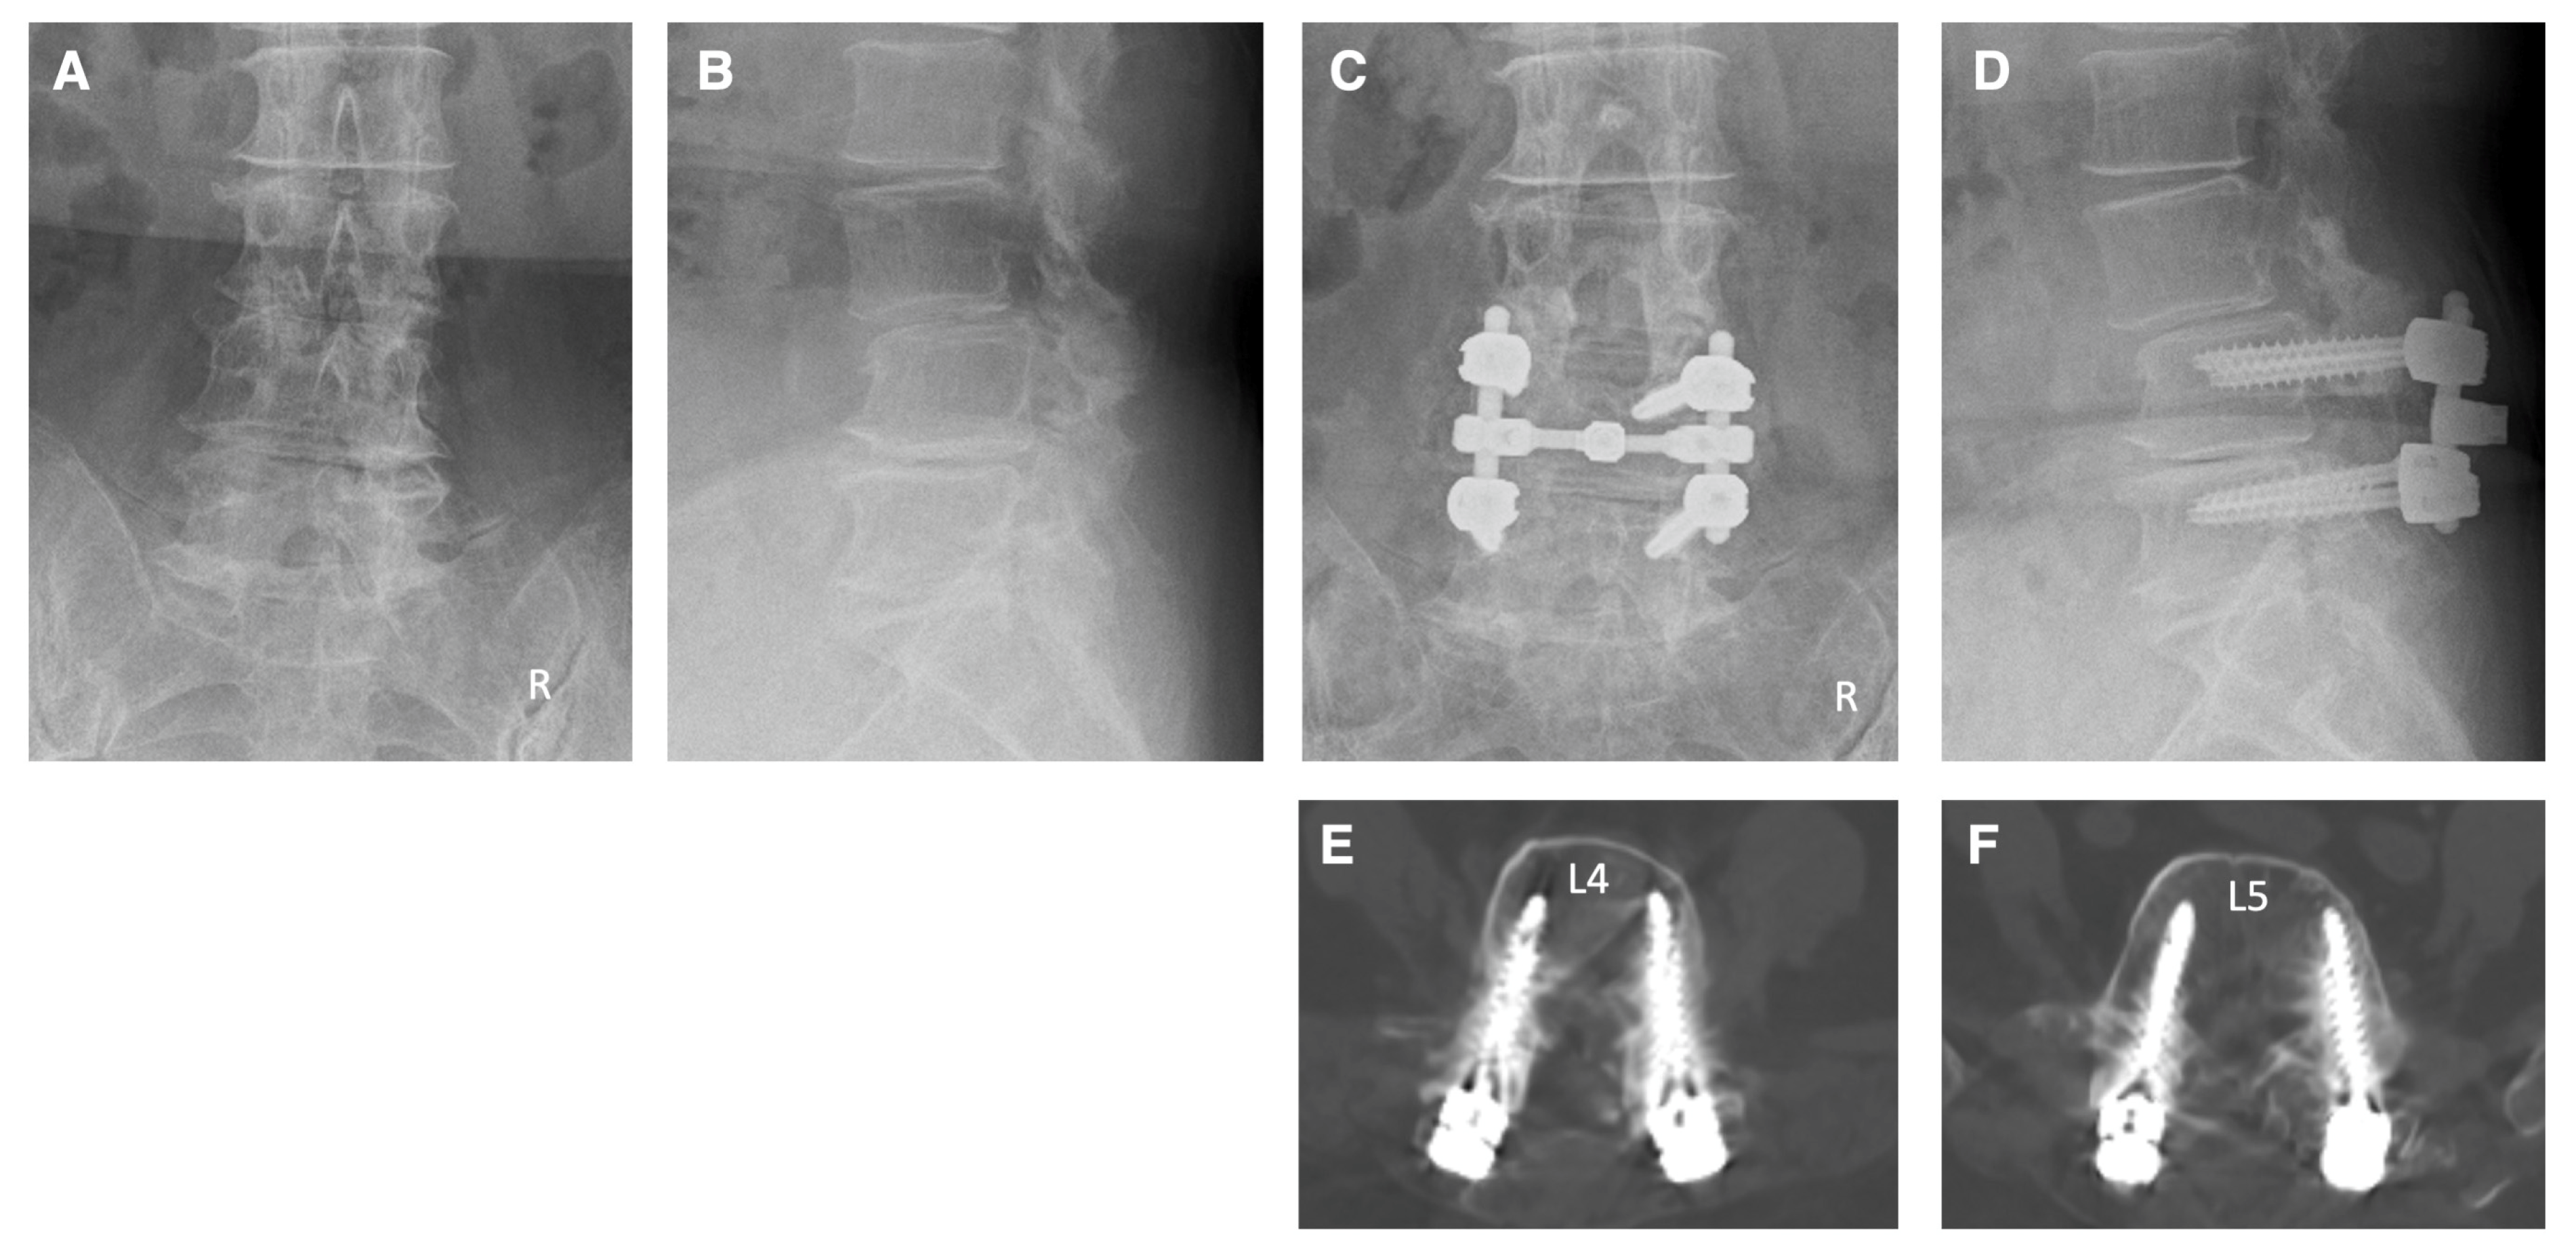

Case 2: A 74-year-old woman came to our hospital with numbness in both of his lower extremities and intermittent claudication. She was diagnosed as having cauda equina syndrome and right L4 radiculopathy due to spinal canal stenosis at the L2–5 levels, foraminal stenosis on the right side at the L4–5 levels, and degenerative spondylolisthesis at the L3. The patient underwent pedicle screw fixation at the L4–5 levels under navigation. Additionally, decompressions of the spinal canal at L2–5 levels and foramen on the right side at the L4–5 levels were performed. Postoperative X-ray and CT images show that the pedicle screws were appropriately inserted (Figure 6). Following the surgery, there was a significant improvement in the numbness of the lower limbs and intermittent claudication.

Figure 6.

Illustrative case 2. (A,B) Preoperative X-ray shows degenerative spondylolisthesis at the L3 and degenerative changes at multiple levels. (C,D) Postoperative X-ray shows pedicle screw fixation at the L4–5 levels and posterior decompression at L2–5 levels. (E,F) Postoperative CT images show that the pedicle screws were appropriately inserted.